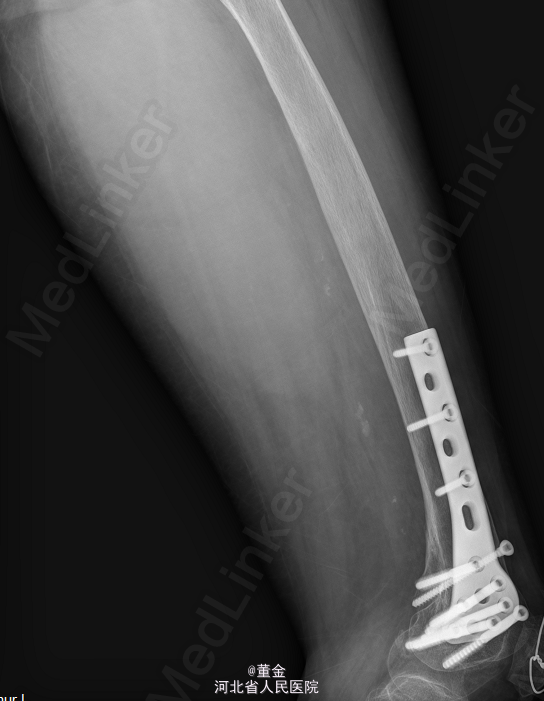

左大腿内侧可见大面积肿块,质硬,活动可,无压痛,表面皮肤无破溃。四肢末端麻木感,末梢血供正常,病理征未引出。MR1.左大腿肌间隙恶性肿瘤,平滑肌肉瘤可能性大,神经鞘瘤恶变待排。2.左股骨下段内固定术后。DR:腰椎内固定术后改变.